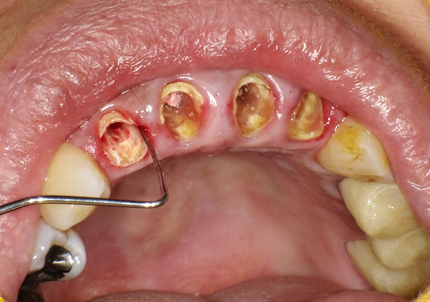

1.初診時口腔内写真(2014年6月)

主訴の左上2番う蝕歯は、抜歯後歯頚線を揃える目的で矯正的挺出の後に抜歯する

3.歯冠長延長術(2014年11月)